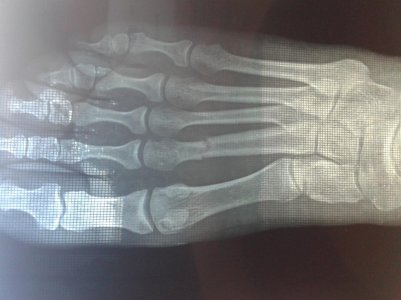

Здравствуйте, доктор! Прошу не отказать мне в консультации по перелому второй плюсневой кости (насколько это возможно в рамках данной темы)

20150703_141553.jpg20150703_141434.jpg20150703_141819.jpg20150703_141646.jpg

Травма случилась 18 мая 2015 от падениы с лестницы. Сразу обратились в травмпункт по месту. Снимок. Перелом со смещением. Дежурный хирург сказал, что смещение в пределах допустимой нормы, поэтому вправлял вручную (вроде как довольно не плохо вправил). Наложили лангету, прописали кальций и сказали явиться на снятие через 4 недели. 20 дней с момента травмы передвигалась только на костылях. По истечении 3х недель начала по-тихоньку пробовать ходить с опорой на пятку прям в лангете. Спустя 4 недели явилась к врачу, как и было сказано. Сначала сняли лангету, потом отправили на контрольный снимок. Результат: кость несколько сместилась, образование мозоли не видно. Снова накладывать гипс не стали, а лишь сказали породолжать пить кальций и бинтовать стопу эластичным бинтом. Нагрузку на пятку разрешили давать дозированную. Сегодня с момента травмы прошло 6 недель. Есть жалобы на отечность ноги после 3-х часовой нагрузки, а так же на изменение больной ноги в цвете - она по сравнению со здоровой выглядит темнее и с оттенком синевы. А так же присутствует щелчок в области перелома если пошевелить пальцами "вверх-вниз". Но я заметила, что этот самый щелчок отсутствует утром и появляется лишь после того, как немного похожу. Продолжаю бинтовать ногу, ходить с опорой на пятку. Хожу достаточно много, т.к у меня маленьки ребенок, за которым нужен постоянный контроль. Поэтому, на ногах я практически с утра до вечера (днем удается полежать 3 часа пока ребенок спит). Помочь сечас физически мне некому. Всвязи с изложенным у меня есть несколько волнующих вопросов: Насколько серьезно смещение? Могут ли быть плохие последствия от столь большой нагрузки на ногу? И насколько тревожен щелчок в области перелома? Возможно есть на снимке хоть какой-то намек на образование мозоли? И почему нога отличается по цвету? Прошу поостить меня за такое кол-во вопоосов. Просто я живу сечас в селе и пока не имею возможности добраться в город к врачу. Доп.информация: Возраст 30 лет, вес 53 кг, рост 166 см. Спасибо Вам!

Фото загрузились в следующем порядке: первая верхняя и снизу под ней - контрольный результат спустя 4 недели. Вторая сверху - сразу после перелома. Третья сверху - сразу после вправления. Благодарю Вас!

Замедленное сращение перелома, нужны ортопедические стельки с выкладкой поперечного свода и удобная обувь, синюшность со временем уйдет, перелом может быть срастется и перестанет щелкать.